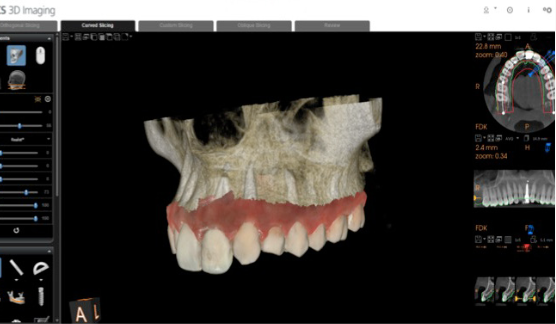

Step 3 — Prosthetic-driven implant planning. This is the key step. The CS 3D Imaging Prosthetic-Driven Implant Planning module automatically merged the CBCT volume with the intraoral scan — aligning hard tissue (bone) with soft tissue (gingiva and teeth) in a single view. The implant was then positioned using a crown-down approach: the ideal restoration position determined the implant axis, not the other way around.

CS 3D Imaging automatically merging CBCT and intraoral scan data for prosthetic-driven planning Implant position planned using crown-down approach in CS 3D Imaging

Step 3 The Prosthetic-Driven Implant Planning module in CS 3D Imaging software automatically merges the CBCT and intraoral scan. The implant is positioned based on the ideal crown position — not just the available bone.